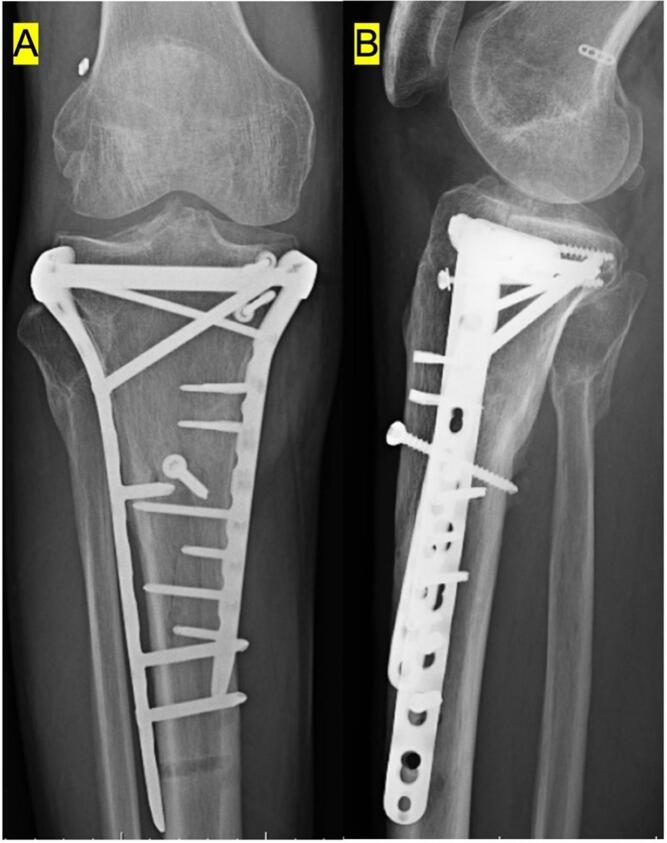

Anterior cruciate ligament reconstruction with retained internal fixation hardware for treating Schatzker type V tibial plateau fracture: Two case reports.

Despite the high incidence of anterior cruciate ligament injury in patients with tibial plateau fractures, we found no reports about anterior cruciate ligament reconstruction with retained internal fixation hardware for these fractures. Herein, we report 2 male patients with Schatzker type V tibial plateau fractures and describe the use of retained hardware for internal fixation in tibia. The patients underwent anterior cruciate ligament reconstruction using outside-in technique for the femoral tunnel. Throughout the follow-up, no radiological symptoms of suspected knee osteoarthritis were observed. Accordingly, surgical intervention can be reduced by creating an independent femoral tunnel.

尽管胫骨平台骨折患者前交叉韧带损伤的发生率很高,但我们未发现有关这些骨折保留内固定硬件进行前交叉韧带重建的报道。在此,我们报告2例Schatzker V型胫骨平台骨折男性患者,并描述在胫骨内固定中使用保留硬件的情况。患者采用经外向内技术建立股骨隧道进行前交叉韧带重建。在整个随访过程中,未观察到疑似膝关节骨关节炎的放射学症状。因此,通过创建独立的股骨隧道可减少手术干预。